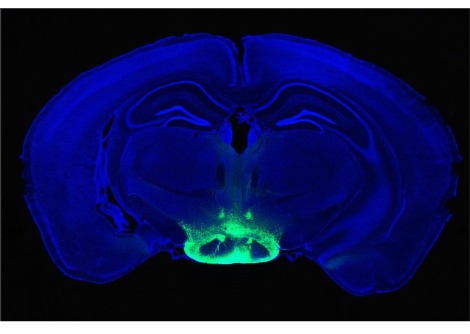

لإنشاء شاشة عرض حية، قام الباحثون بتعديل الخلايا الجذعية للبشرة وراثيًا بحيث تستجيب لإشارات الالتهاب داخل الجسم. عند تنشيط مسار رئيسي مرتبط بالالتهاب، يُعرف باسم NF-κB، تُنتج الخلايا المُهندسة بروتينًا فلوريًا أخضر.

ثم استُخدمت هذه الخلايا المُعدّلة لزراعة أنسجة جلدية، زُرعت على فئران. بعد التئام الطعوم واندماجها مع الأنسجة المحيطة، تصرفت البشرة المُهندسة بشكل مشابه للبشرة الطبيعية، باستثناء فرق جوهري واحد. فعندما يحدث التهاب داخل الجسم، تبدأ المنطقة المزروعة بالتوهج باللون الأخضر.

يُترجم هذا التوهج إشارة جزيئية غير مرئية إلى إشارة مرئية، مما يسمح بقراءة النشاط البيولوجي الداخلي مباشرةً على سطح الجلد. ولأن المستشعر مصنوع من خلايا جذعية حية، فهو لا يعتمد على الإلكترونيات أو مصادر الطاقة أو الاستبدال الدوري. ومع تجدد الجلد بشكل طبيعي، تستمر الخلايا الجذعية المُهندسة في إنتاج خلايا استشعار جديدة.

وقال شوجي تاكيوتشي من جامعة طوكيو في بيان صحفي: "على عكس الأجهزة التقليدية التي تتطلب مصادر طاقة أو استبدالًا دوريًا، يُحافظ الجسم نفسه على هذا النظام بيولوجيًا. في تجاربنا، استمرت وظيفة المستشعر لأكثر من 200 يوم، حيث جددت الخلايا الجذعية المُهندسة البشرة باستمرار."